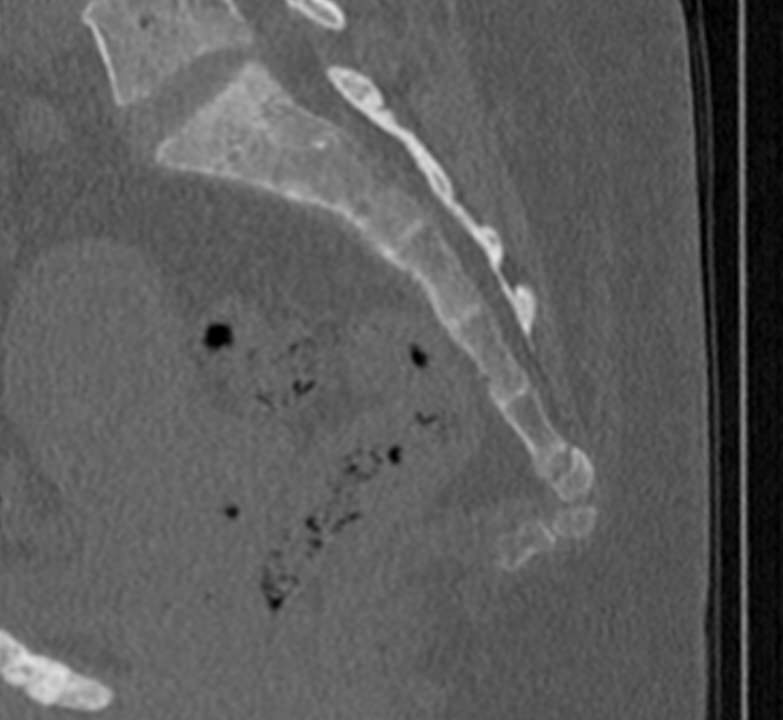

Для диагностики даже незначительных патологических изменений в различных отделах позвоночника, особенно в случае распространенного поражения, применяется один из современных наиболее информативных методов обследования – мультиспиральная компьютерная томография всего позвоночника. Методика основана на использовании проникающей способности рентгеновских лучей через органы и ткани человека и позволяет получить подробное изображение всех структур позвоночного столба. В комплексное обследование входит исследование шейного, грудного, пояснично-крестцового отделов позвоночника и копчика.

В медицинских центрах «Доступная медицина» сканирование всего позвоночника выполняется на новейших мультиспиральных компьютерных томографах последнего поколения TOSHIBA AQUILION в различных модификациях. Особенностью данных аппаратов является их способность проводить от 64 до 128 тончайших срезов одномоментно с минимальной толщиной от 0,5 мм.

Увеличенное количество высокочувствительных детекторов, которыми оснащены томографы, позволяет получать послойные снимки высокого качества с большой скоростью. Эта особенность данных аппаратов обеспечивает быстроту выполнения сканирования. При этом пациент получает минимальную дозу облучения, что имеет важное значение, особенно при такой обширной зоне исследования, как позвоночный столб.